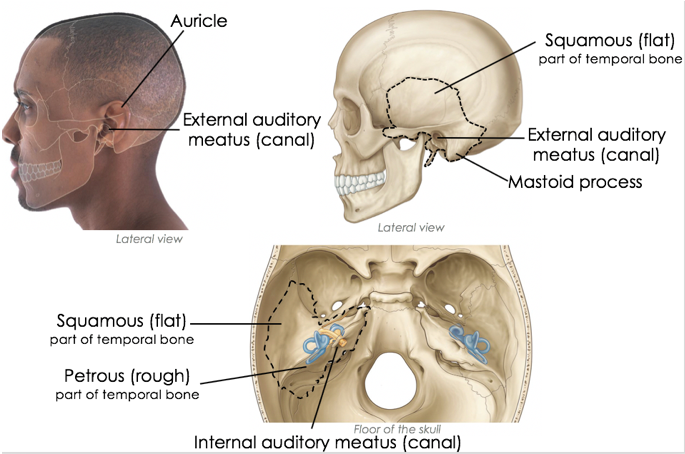

Which skull bone does the ear sit around?

Temporal bone

What 2 parts can the temporal bone be divided into?

- Squamous; lateral, flat portion

- Petrous; rough portion

The external ear can be divided functionally and structurally into two parts. What are they?

- Auricle (or pinna)

- External acoustic meatus

Describe the composition of the external acoustic meatus

- Lateral 1/3rd of the canal is cartilaginous

- Medial 2/3rds of the canal is bony, made up of temporal bone